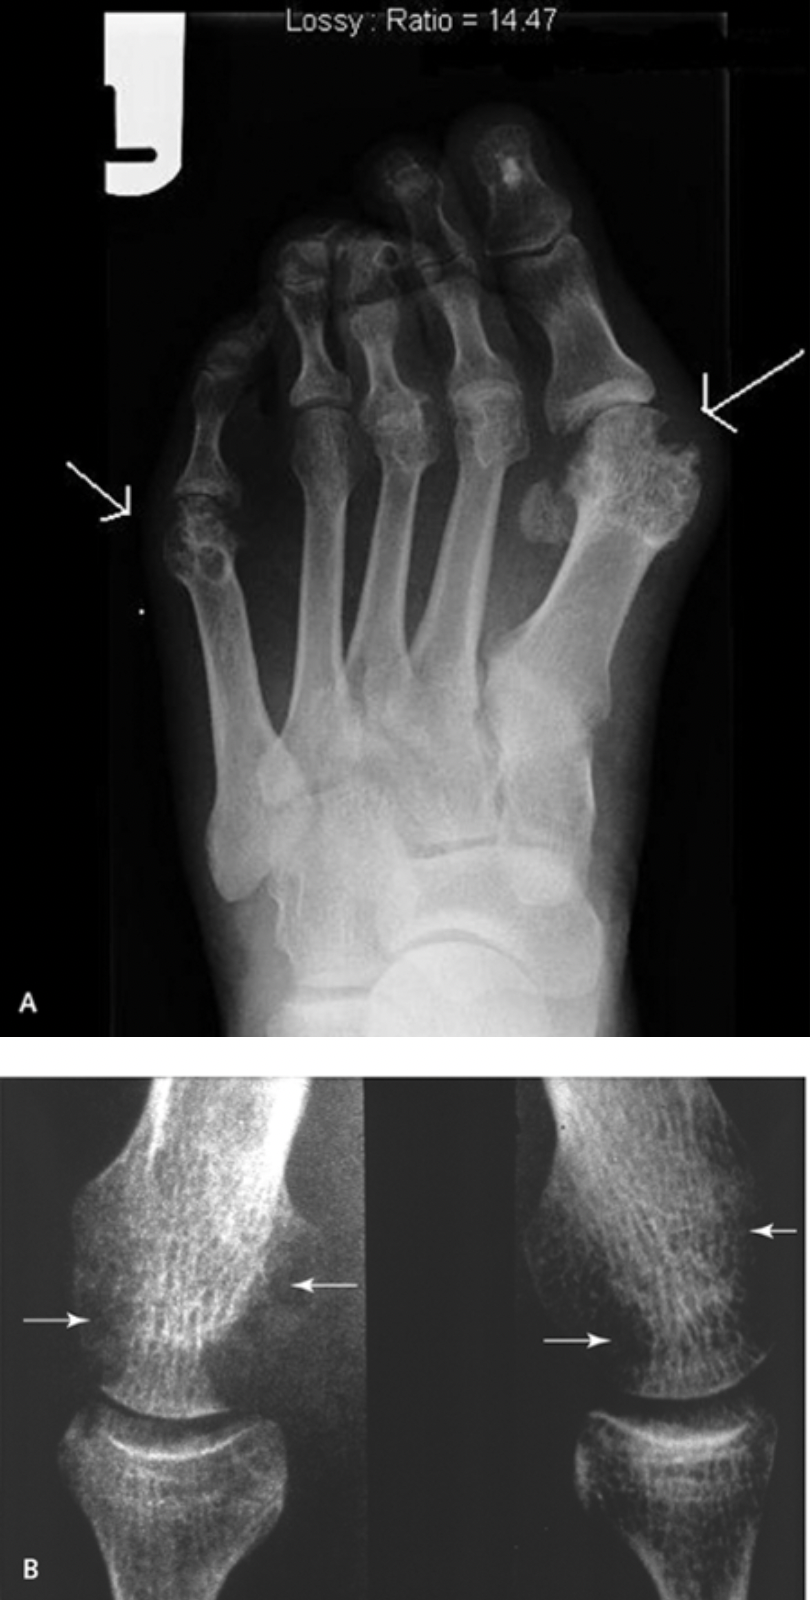

Which deformity is this?

A

Swan neck